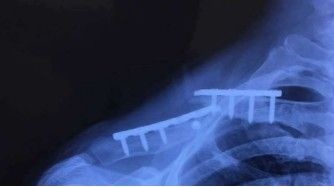

3.5 Pjanċi ta 'kompressjoni sistematiċi, pjanċi ta' rikostruzzjoni, jew LCPs tal-plastik jistgħu jintużaw biex jiffissaw ksur tal-klavikula. Il-pjanċi jitqiegħdu bla xkiel fuq jew qabel il-klavikula. Il-pjanċi huma aktar b'saħħithom f'korrimenti bijomekkaniċi meta jitqiegħdu superjuri, speċjalment jekk hemm ksur imqatta 'taħt, u huma aktar sempliċi biex jiġu viżwalizzati. L-iffissar bikortikali tal-viti hija meħtieġa, u t-toqob għandhom jittaqqbu b'attenzjoni kbira, peress li hemm riskju ta 'korriment fin-nervituri u l-vini tad-demm hawn taħt. Vantaġġi: tħaffir sikur tal-kanal tal-kamin tal-pjanċa anterjuri, appożizzjoni tal-pjanċa, kontorn faċli.

L-għażla tal-impjanti tal-pjanċa tiddependi fuq id-daqs tal-blokka tal-għadam laterali. Minimu ta' 3 viti bikortikali huma meħtieġa għall-blokk laterali tal-għadam. Idealment, il-viti tat-tensjoni għandhom jintużaw għal ksur oblikwu. Jekk il-blokka tal-għadam hija żgħira wisq għall-iffissar, tista 'tintuża pjanċa tal-ganċ tal-klavikula.